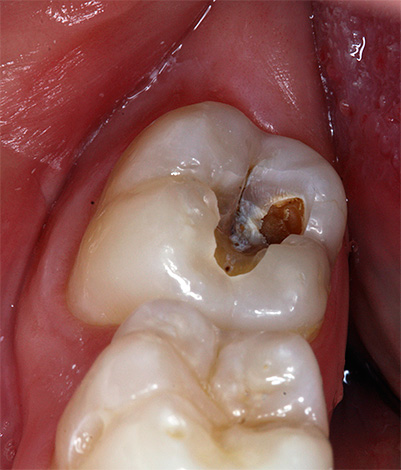

Foto dei residui di polpa rimossi dal canale radicolare del dente:

Per gli stessi motivi, è impossibile eseguire l'amputazione vitale preservando solo la polpa della radice, poiché è quasi sempre già coinvolta nei processi di necrosi.